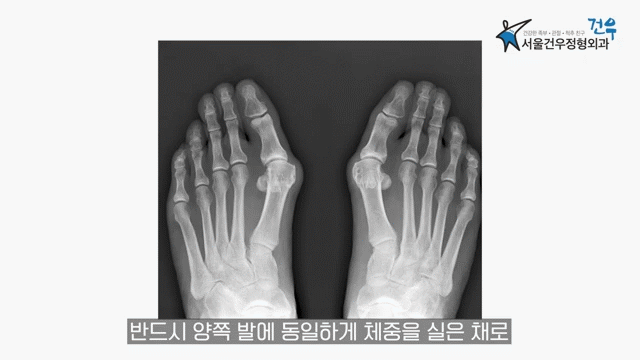

그러나 정확한 평가는 영상 검사가 필요합니다. 진단 시 중요한 점은 반드시 체중을 실은 상태에서 양측 발을 동시에 촬영하는 X-ray 검사를 시행해야 한다는 것입니다.

체중을 실지 않은 상태에서 X-ray 검사는 실제 보행 시의 정렬을 반영하지 못하므로 정확도가 떨어질 수 있습니다.